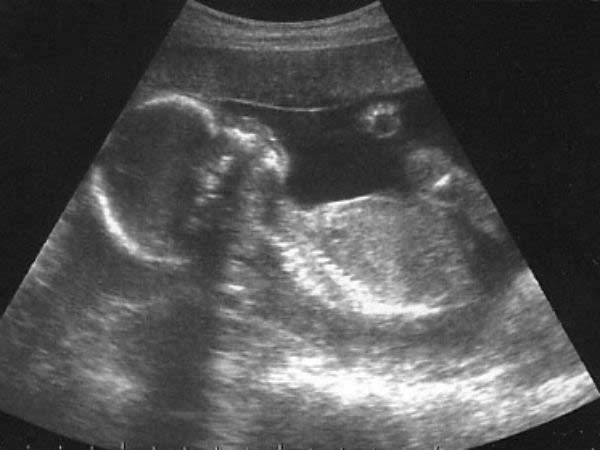

பெண் சிசு கொலைகளை தடுக்கும் விதமாக குழந்தையின் பாலினத்தை ஸ்கேனில் மறைப்பதற்கான மென்பொருள் தயாரிக்கப்பட்டு வருவதாக தமிழக அரசு தெரிவித்துள்ளது.

சென்னை: பெண் சிசு கொலைகளை தடுக்கும் விதமாக குழந்தையின் பாலினத்தை ஸ்கேனில் மறைப்பதற்கான மென்பொருள் தயாரிக்கப்பட்டு வருவதாக தமிழக அரசு தெரிவித்துள்ளது. சென்னை ஐஐடியுடன் இணைந்து அரசு இந்த மென்பொருளை உருவாக்கி வருவதாக தமிழக குடும்பநலத்துறை இயக்குநர் மருத்துவர் பானு கூறியுள்ளார்.

இந்தியாவிலேயே முதல் முறையாக குழந்தையின் பாலினத்தை கண்டறிவதை தடுக்க புதிய மென்பொருளை தமிழக அரசு தயாரித்து வருகிறது. ஸ்கேன் செய்யும் போது குழந்தையின் பிறப்புறுப்பு மட்டும் தெரியாத வகையில் மாஸ்க் செய்வதற்கான மென்பொருள் தயாரிக்கப்பட்டு வருவதாக தமிழக குடும்பநலத்துறை இயக்குநர் மருத்துவர் பானு கூறியுள்ளார்.

சென்னை ஐஐடியுடன் இணைந்து அரசு உருவாக்கி வரும் இந்த மென்பொருள் மூலம் குழந்தையின் பாலினத்தை மட்டும் ஸ்கேனின் போதே மாஸ்க் செய்யும் சாப்ட்வேர் ஸ்கேன் மெஷின்களில் பொருத்தப்பட்ட பின்னரே ஸ்கேன் மையங்களுக்கு அனுப்பப்படும் என்று பானு தெரிவித்துள்ளார்.

மென்பொருள் பரிசோதனையில் இருப்பதாகவும் இது வெற்றி தரும் பட்சத்தில் தமிழகத்தில் உள்ள ஸ்கேன் மெஷின்களில் இது பொருத்தப்படும் என்றும் பிற மாநிலங்களில் இருந்து தமிழகத்திற்கு கொண்டு வரப்படும் அனைத்து ஸ்கேன் மெஷின்களிலும் இது புதிதாக சேர்க்கப்பட்டு அதன் பின்னர் மையங்களுக்கு அனுப்பி வைக்கப்படும் என்றார்.